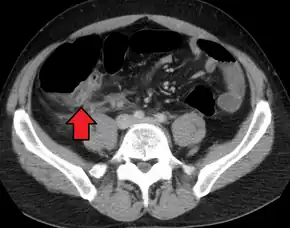

Computed tomography

Where it is readily available, computed tomography (CT) has become frequently used, especially in people whose diagnosis is not obvious on history and physical examination. Although some concerns about interpretation are identified, a 2019 Cochrane review found that sensitivity and specificity of CT for the diagnosis of acute appendicitis in adults was high.[61] Concerns about radiation tend to limit use of CT in pregnant women and children, especially with the increasingly widespread usage of MRI.[62][63]

The accurate diagnosis of appendicitis is multi-tiered, with the size of the appendix having the strongest positive predictive value, while indirect features can either increase or decrease sensitivity and specificity. A size of over 6 mm is both 95% sensitive and specific for appendicitis.[64]

However, because the appendix can be filled with fecal material, causing intraluminal distention, this criterion has shown limited utility in more recent meta-analyses.[65] This is as opposed to ultrasound, in which the wall of the appendix can be more easily distinguished from intraluminal feces. In such scenarios, ancillary features such as increased wall enhancement as compared to adjacent bowel and inflammation of the surrounding fat, or fat stranding, can be supportive of the diagnosis. However, their absence does not preclude it. In severe cases with perforation, an adjacent phlegmon or abscess can be seen. Dense fluid layering in the pelvis can also result, related to either pus or enteric spillage. When patients are thin or younger, the relative absence of fat can make the appendix and surrounding fat stranding difficult to see.[65]